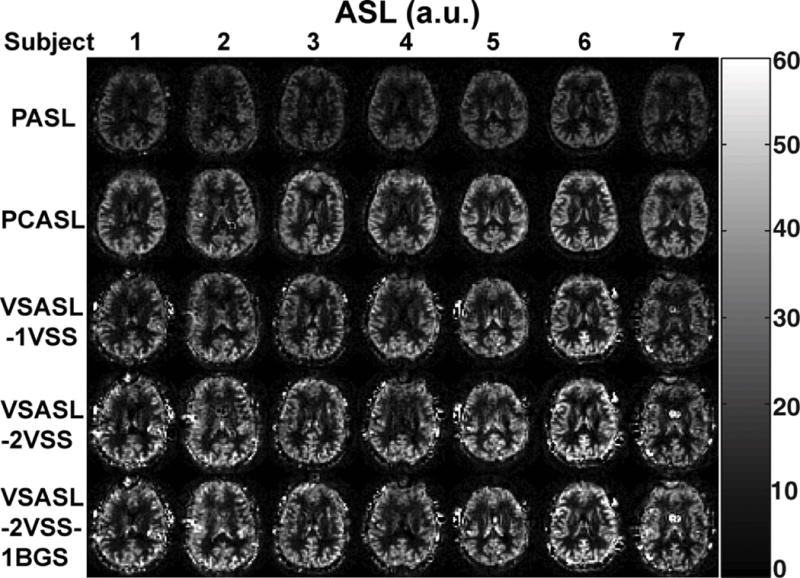

The mmVSASL approach is another example of how the idea of accumulating signal before acquisition can be used to create new ASL sequences and boost the perfusion signal (137). In this sequence, as also suggested by Norris and Schwarzbauer in their original paper (95), the velocity-selective saturation (VSS) module is repeated several times before image acquisition (Fig. 13), similar to the Multiple Pulsed Imaging Labeling (MPIL) technique (36). Simulations and experimental results on human brain (Fig. 14) suggest that mmVSASL with two VSS modules can reach 20% SNR improvement compared to the VSASL with a single VSS module, which is significantly higher than PASL and comparable to PCASL in terms of SNR (Fig. 14). The mmVSASL approach can also be extended to a steady state version following the cine-ASL and SPIL ideas.

Figure 14.

Examples of perfusion maps measured with different preparations in seven subjects. The maps from top to bottom were acquired with PASL, PCASL, VSASL-1VSS (single VSS), VSASL-2VSS (double VSS), and VSASL-2VSS-1BGS (double VSS with background suppression (BGS)). Reproduced with permission from Guo J et. al. Magn Reson Med 2015;74(3):694-705.